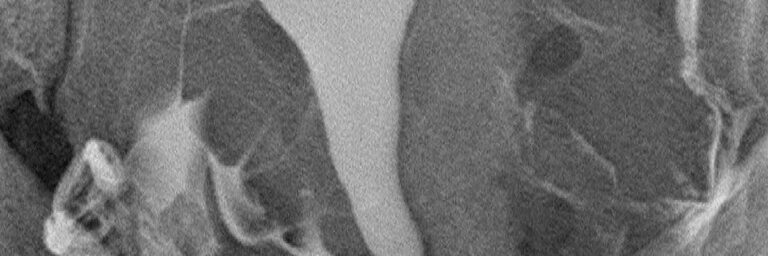

HSG (rahim filmi) incelemesi 50 seneden uzun süredir bilinmekte ve uygulanmaktadır. Buna karşılık son 20 yılda pek çok teknolojik ilerleme olmuş, buna uygun aparatlar üretilmiş ve yeni teknikler geliştirilmiştir. Söz konusu yenilikler şu başlıklar altında toplanabilir:

1-Dijital röntgen cihazları

2-C kollu dijital röntgen cihazları

3-Film banyosu ihtiyacını ortadan kaldıran termal veya lazer film baskı cihazları

4-Görüntülerin hekimlere bilgisayar ortamında gönderilmesini ve arşivlenebilmesini sağlayan dijital teknolojiler

5-Alerji riski düşük, yağ embolisi ve granülom oluşturma riski bulunmayan, osmolaritesi, viskositesi düzenlenmiş yeni nesil suda çözünebilir iyotlu kontrast maddeler

6-Kontrast maddeyi rahim boşluğuna veya doğrudan tüplerin içine doldurabilmek için geliştirilen ince, yumuşak, ucu balonlu veya balonsuz kateterler.

Bütün bu yenilikler, ağrısız rahim filmi çekimini mümkün kılmakla kalmamış, olumsuz yan etkiler çok azalmış, bazı komplikasyonlar ortadan kalkmış, gerek uygulamayı yapan hekimlerin gerekse hastaların maruz kaldığı radyasyon miktarları belirgin derecede düşmüş, film kalitesi yükselmiş, doğru teşhiş oranı yükselmiş, inceleme sayılarının artmasıyla birlikte birim maliyetler ve fiyatlar göreceli olarak düşmüştür. Yeni tekniklerin oldukça yüklü yatırım maliyetinin olmasına rağmen bir paradoks olarak eski teknik kullanılarak yapılan standart incelemelerin toplam birim maliyeti yeni tekniklerden daha ucuz olamamaktadır.

Sonuç olarak, rahim filmi çekimi için C kollu dijital röntgen cihazı bulunan ve yukarıda sayılan yeni teknikleri kullanan merkezler tercih edilmelidir.